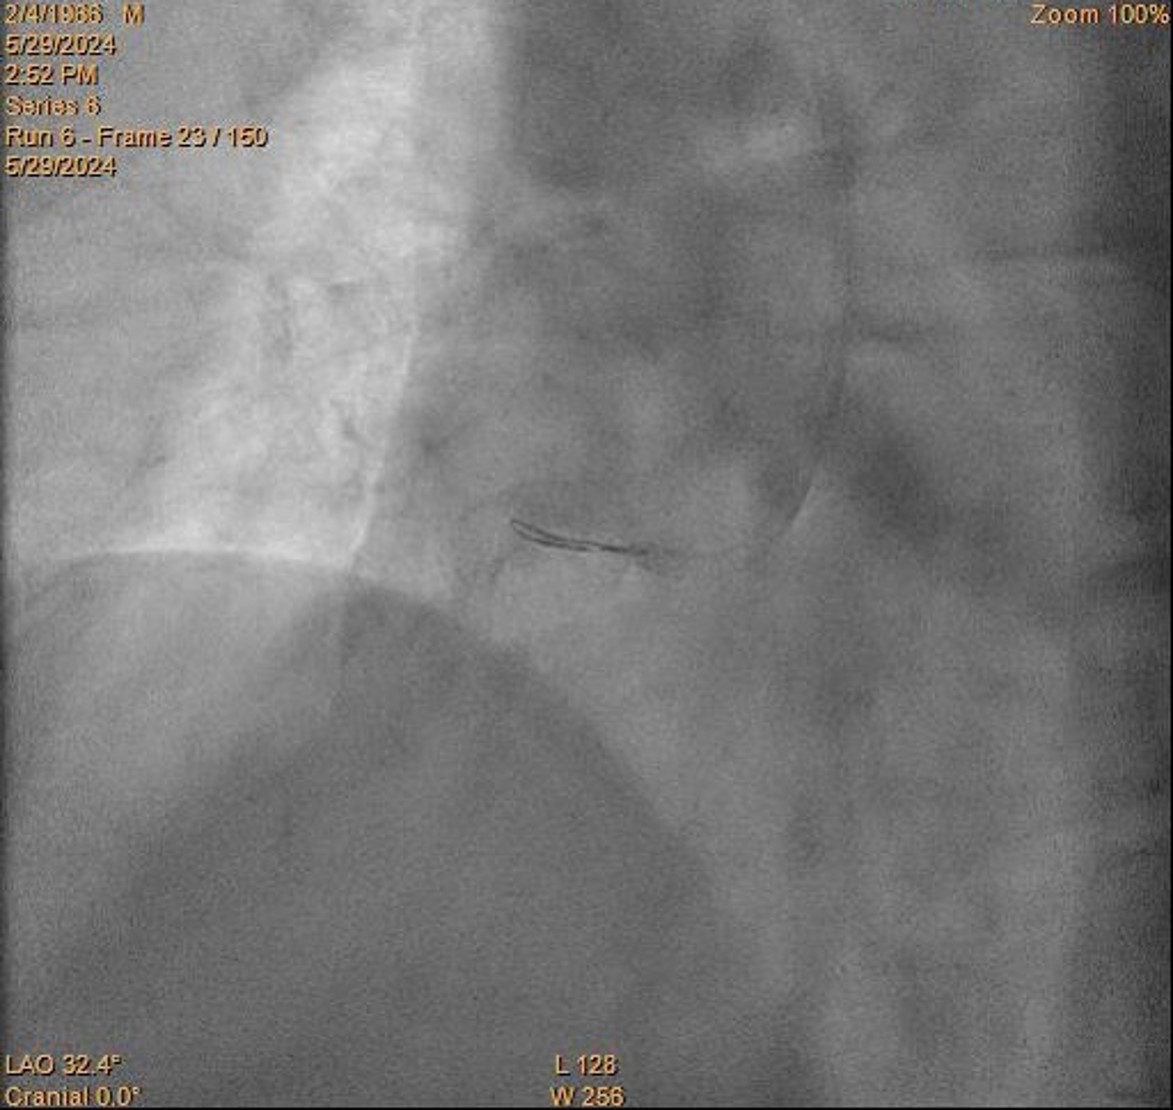

Patient reported ongoing pain. Decided to proceed with stenting with the acknowledgement of likely malapposed proximal stent. Onyx Frontier 5.0/30 is deployed over proximal-mid RCA.. IVUS showed no stent edge dissection and malapposed proximal stent edge as expected.

The stent is dilated with 6.0 balloon. Integrellin infusion is given. TIMI III flow is restored.

Restudy coro is performed 3 months later. Very difficult RCA wiring is noted. RCA is wired with NS Runthrough, but failed to deliver IVUS. Second Runthrough wire crossed with crusade. IVUS showed stent landed on distal edge of aneurysm. Size of aneursym too big to be measured by IVUS and stented. Thrombus inside aneruysms is noted.

Reviewed is team discussion, it is decided for lifelong anticoagulation and not for further stenting proximally

Despite balloon dilatation and thrombectomy, flow is yet to be restored. Flow is restored after stenting. IVUS shows the aneurysm is so big beyond the limit of the machine, with thrombus inside. Stent landed on distal edge of aneurysm. Restudy coro showed TIMI III flow. Difficult rewiring requires use of crusade and 2nd wire. IVUS shows stent malapposed. No available coronary stent is big enough to cover the aneurysm. Reviewed in team meeting, it is decided for lifelong anticoagulation.

Despite balloon dilatation and thrombectomy, flow is yet to be restored. Flow is restored after stenting. IVUS shows the aneurysm is so big beyond the limit of the machine, with thrombus inside. Stent landed on distal edge of aneurysm. Restudy coro showed TIMI III flow. Difficult rewiring requires use of crusade and 2nd wire. IVUS shows stent malapposed. No available coronary stent is big enough to cover the aneurysm. Reviewed in team meeting, it is decided for lifelong anticoagulation.